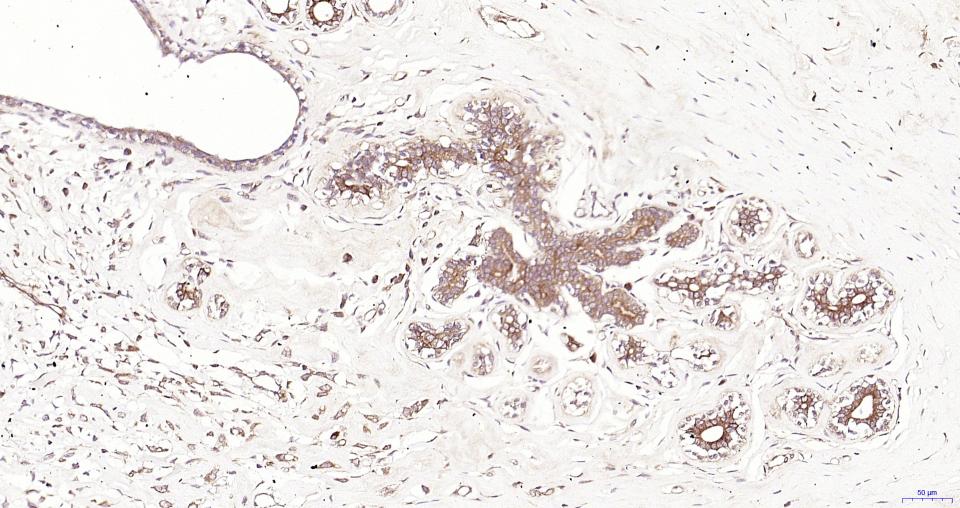

Paraformaldehyde-fixed, paraffin embedded Human Breast Cancer; Antigen retrieval by boiling in sodium citrate buffer (pH6.0) for 15 min; Antibody incubation with MyD88 Monoclonal Antibody, Unconjugated(bsm-61269R) at 1:200 overnight at 4°C, followed by conjugation to the SP Kit(Rabbit, SP-0023) and DAB (C-0010) staining.